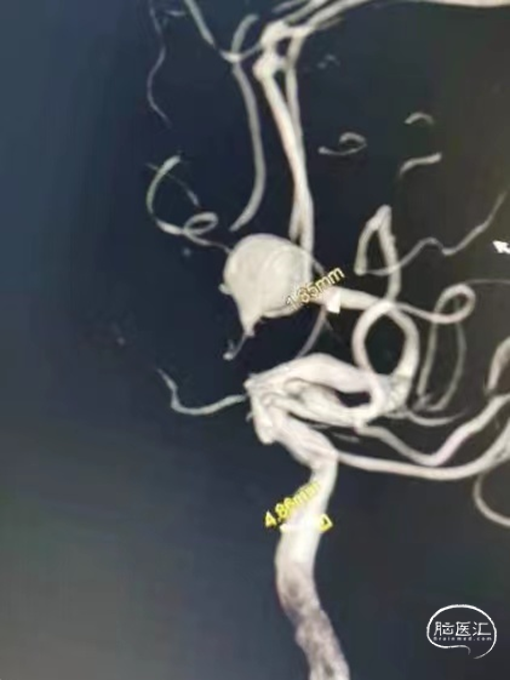

DSA结果:造影发现前交通动脉瘤,3D成像测量直径12mm,载瘤动脉直径1.85mm

术前3D-DSA造影:测量动脉瘤直径在12mm,载瘤动脉直径1.85mm。